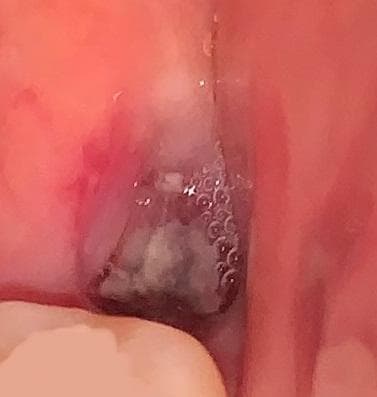

사랑니 발치했는데 드라이소켓 가능성이 있나요?

똑바로 난 사랑니라 딱히 절개없이 바로 발치하였습니다.

발치한지 1주일정도가 되었는데도 가만히 있어도 발치부위 잇몸과 턱이 욱신거리는 느낌이 계속됩니다.

드라이소켓일 가능성이 있을까요? 아니면 발치부위가 치유되는 과정일까요?